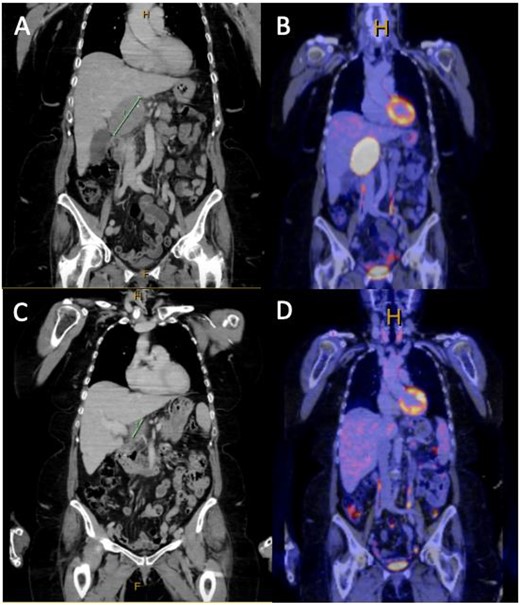

(A and B) Coronal slice of surveillance CT and FDG PET showing a 44 × 56 × 78 mm PET avid exophytic lesion abutting the caudate lobe extending into portocaval space suspicious for metastatic melanoma, given the patients history of cutaneous melanoma; (C and D) coronal slice of CT and FDG PET post three cycles of dual immunotherapy, showing complete metabolic response and significant reduction in size of the metastatic lesion demonstrated in (A) and (B).

Given the high FDG avidity of the caudate lesion endoscopic ultrasound and fine needle aspirate, biopsies were arranged. Histopathology from this biopsy was consistent with a diagnosis of metastatic melanoma. Based on the imaging and tissue diagnosis, the patient was discussed at the HPB multidisciplinary team meeting, and decision was made for the commencement of immunotherapy with potential for surgical resection if there is adequate disease response. The patient was proceeded with dual immunotherapy (ipilimumab and nivolumab), and upon completion of three cycles of immunotherapy, there was a repeat PET/CT scan. The repeat PET scan showed complete metabolic response of the lesion abutting the caudate lobe, which was no longer FDG avid and had reduced in size significantly. The patient underwent a portohepatic lymphadenectomy and cholecystectomy. No macroscopic disease was observed within the peritoneal cavity and a hard 30 × 40 mm nodule was resected from within the hepatoduodenal ligament along with a lymph node packet containing several visible nodes from porta-hepatis to duodenum, including hepatic nodes. Histopathology from this operation showed granulomatous reaction with no viable malignancy remaining. The patient was discharged from HPB surgical clinics 4 weeks postoperatively with an appropriate medical oncology follow-up. The patient is currently 2 months postsurgery and has commenced single-agent immunotherapy with nivolumab as an adjuvant treatment with a planned repeat PET scan when treatment is completed.